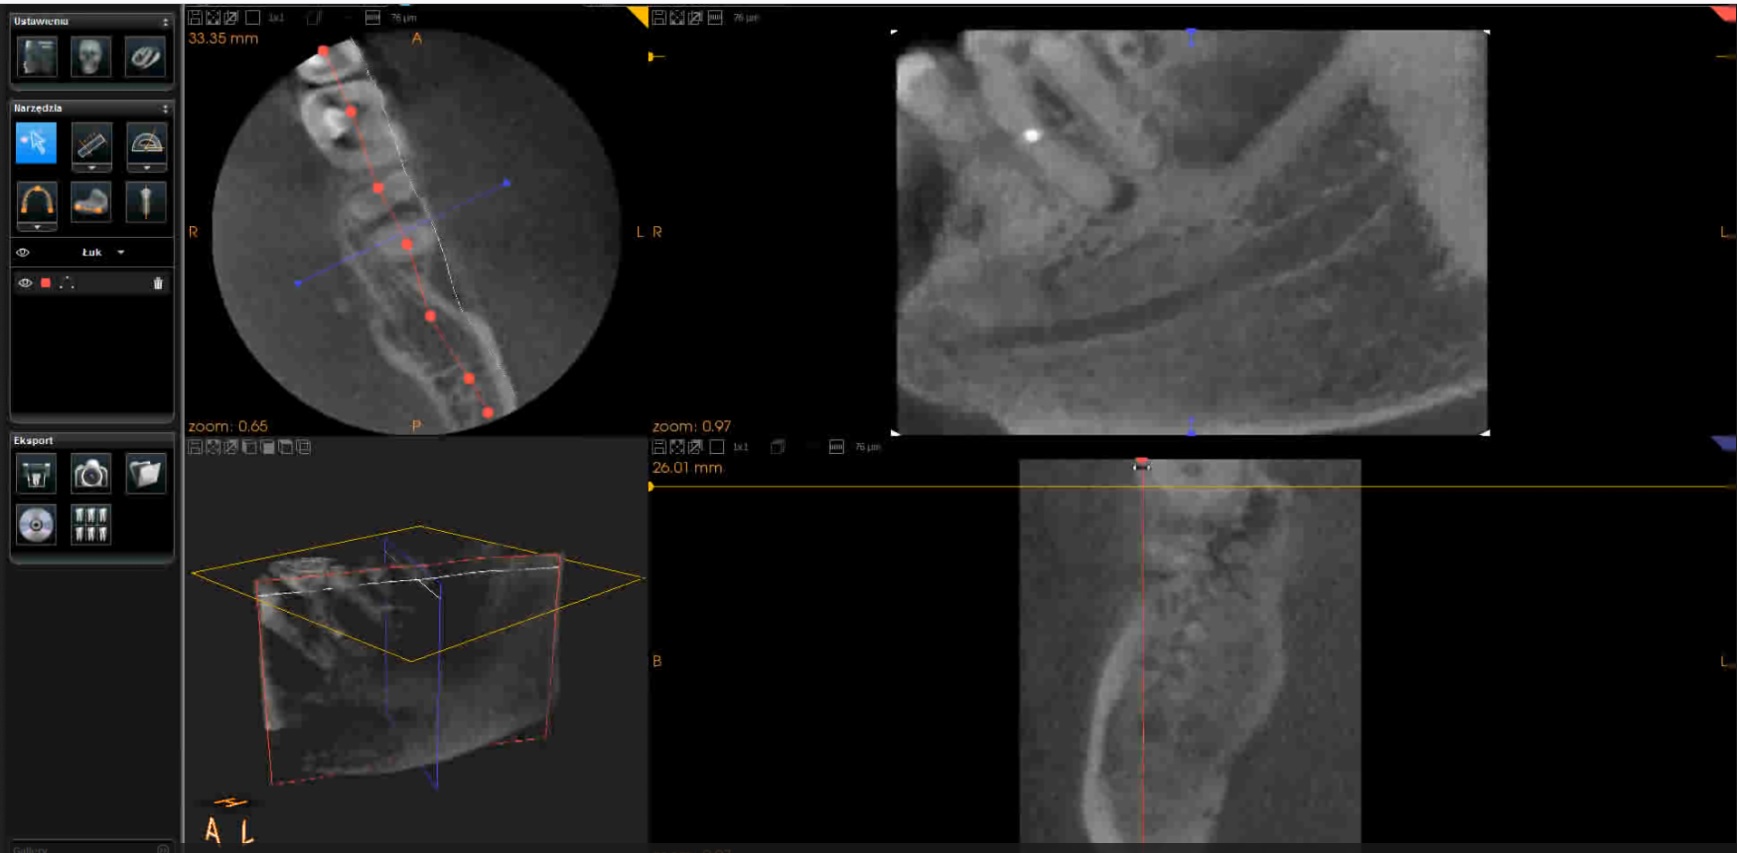

2

Film 2. Badanie CBCT potwierdzające lokalizację złamanych fragmentów narzędzi oraz perforację korzeni zębów w płaszczyźnie strzałkowej. W filmie kursorem wskazywane są kolejne miejsca preparacji przestrzeni dla implantów ortodontycznych. Zmieniający się obraz przekroju strzałkowego widoczny jest w prawej, górnej części ekranu.